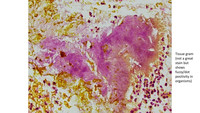

H&E Staining Sulfur granule

Patient presented with peritoneal nodules, that was biopsied and confirmed Actinonomycosis.